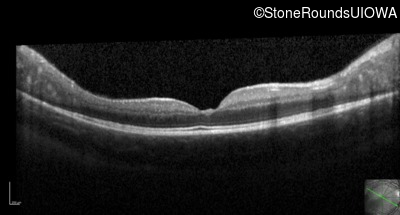

Optical Coherence Tomography - Right - 20/32

Exemplar / OCT Stack